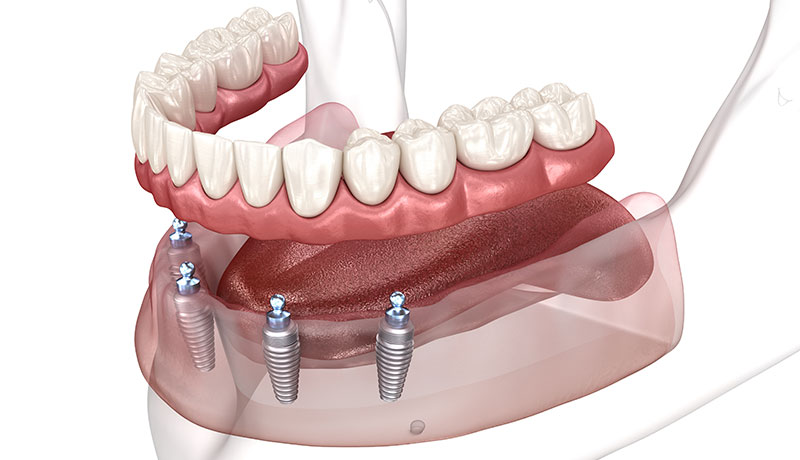

歯がボロボロ、歯が無い方も

諦めなくて大丈夫

当院では、歯がほとんど残っていない方にも対応可能なオールオン4にも対応しております。オールオン4とは、片顎最小4本のインプラントで10本~12本の人工歯を支える治療方法であり、見た目、機能ともに自然な仕上がりとなります。